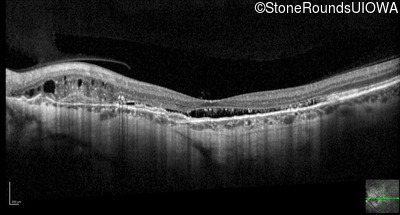

Optical Coherence Tomography - Right - 20/20 -3 sc

Exemplar / OCT Stack

OCT Stack